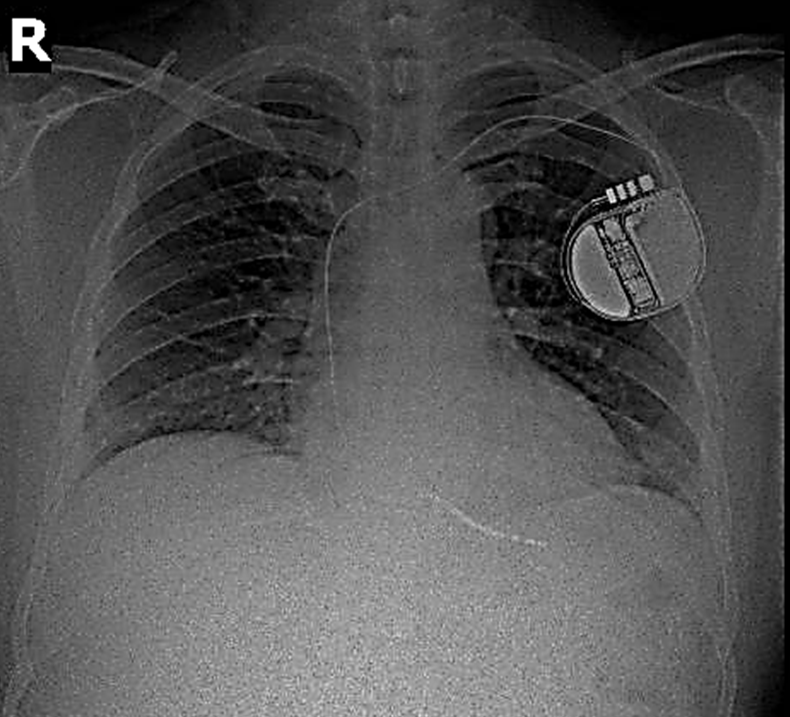

Hình ảnh máy phá rung tim trên phim chụp Xquang. Ảnh: BVCC

Sau đó người bệnh đã được cấy máy khử rung tim (ICD) – một thiết bị nhỏ đặt trong lồng ngực, có nhiệm vụ phát hiện và ngăn chặn kịp thời các cơn rối loạn nhịp tim nguy hiểm bằng xung điện.